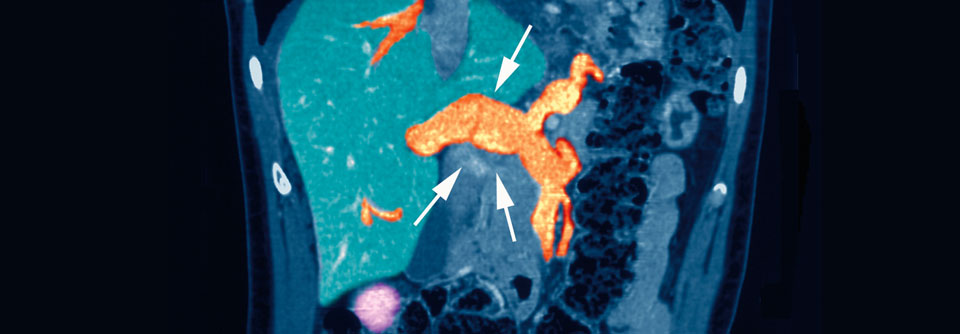

Bei gesicherter Thrombose beginnt die Therapie mit NMH, Fondaparinux, Apixaban oder Rivaroxaban. Bei gesicherter Thrombose beginnt die Therapie mit NMH, Fondaparinux, Apixaban oder Rivaroxaban. © Axel Kock – stock.adobe.com